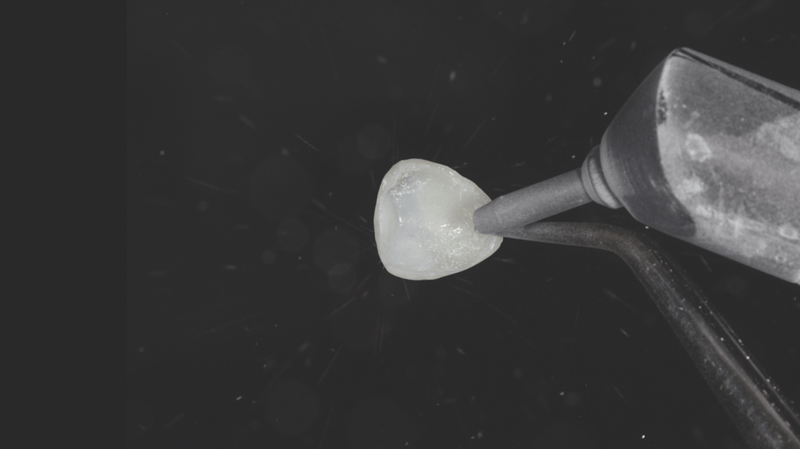

- Verwijderen van de composietveneers: De composietveneers werden verwijderd.

- Contoureren van de rand: Voor de afwerking van de randen werd een fijne, naaldvormige diamantboor gebruikt om de gewenste vorm te krijgen.

- Polijsten en prepareren voor het cementeren: De veneers werden gecontoureerd en gepolijst met de Jiffy™ Natural-polijstset en zo klaargemaakt voor het cementeren.

- Prepareren van het binnenvlak: Het binnenvlak van de veneer werd gezandstraald. Voor deze stap kan eventueel ook Ultra-Etch™-etsmiddel met 35% fosforzuur worden gebruikt.

- Adhesieflaag: Op het binnenvlak werd een laag Peak™ Universal Bond-adhesief aangebracht.

- Uitdunnen en uitharden van de adhesief: De adhesief werd uitgeblazen met lucht, vervolgens uitgehard met de VALO™ X-polymerisatielamp, gedurende 3 seconden op de Xtra Power-stand.